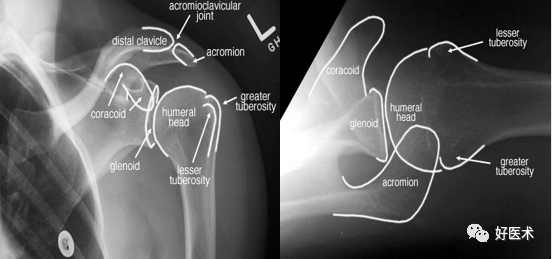

肩关节骨骼构成

三块骨:肩胛骨、锁骨、肱骨

两个关节:

肩锁关节

盂肱关节